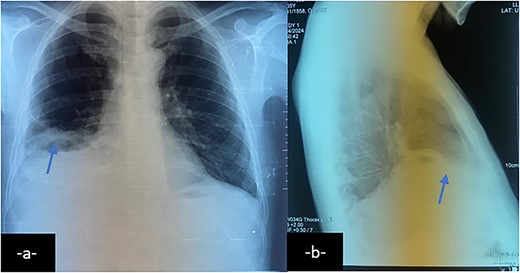

Chest X-ray on postero-anterior (a) and lateral views shows right basal atelectasis of the lung, right pleural effusion and sub phrenic collection with air-fluid level (arrow).

Chest X-ray may reveal dense opacities in the right lower lobe.